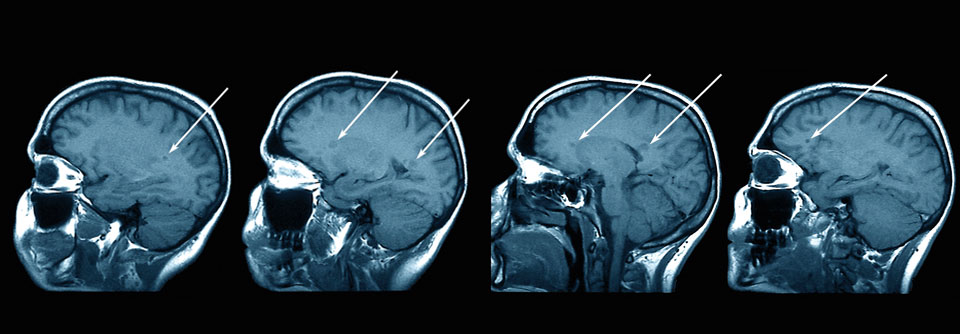

Zu selten kommen gezielte Therapien unter anderem bei Fatigue oder kognitiven Störungen zum Einsatz. Zu selten kommen gezielte Therapien unter anderem bei Fatigue oder kognitiven Störungen zum Einsatz. © fran_kie – stock.adobe.com

Die meisten Patienten mit Multipler Sklerose erhalten heute eine krankheitsmodifizierende Immuntherapie. Doch die typischen Symptome wie Fatigue, kognitive Beeinträchtigungen oder Blasenstörungen werden noch immer unzureichend behandelt.